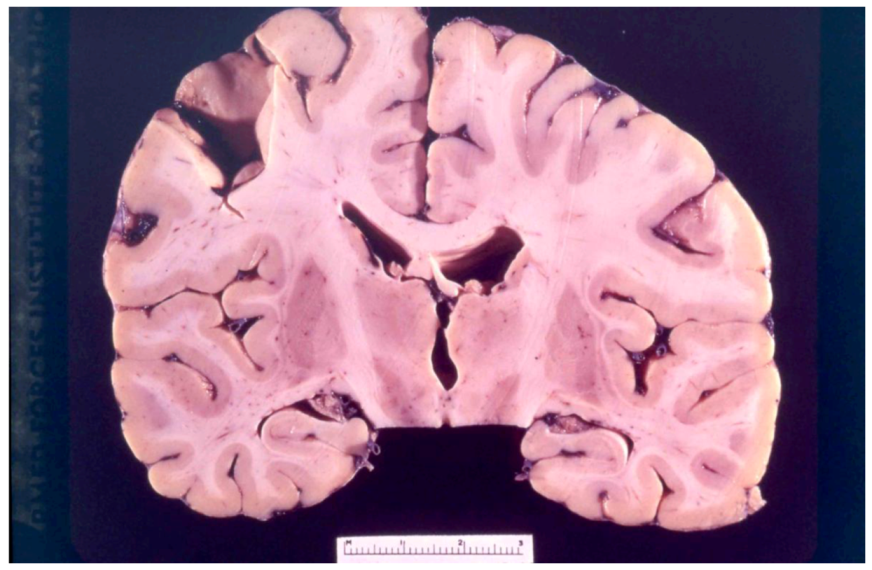

8. Neuropathology